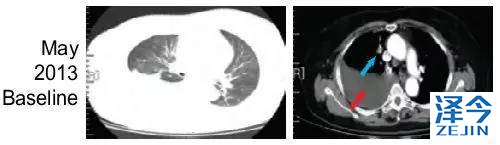

患者,女,62岁,无吸烟史,2013年5月因胸腔积液入院检查并治疗,被确诊为Ⅳ期肺腺癌。

化疗,一代TKI治疗后,病情依旧进展

患者先进行化疗,基因检测显示为EGFR 19号外显子缺失,开始使用一代TKI药物治疗。一代TKI耐药后,发现患者出现T790M突变。